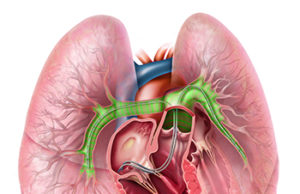

Gore Excluder iliac branch endoprosthesis granted FDA approval

The Gore Excluder iliac branch endoprosthesis has become the first off-the-shelf aortic branch to be approved by the US Food and Drug Administration (FDA), according to a company release.